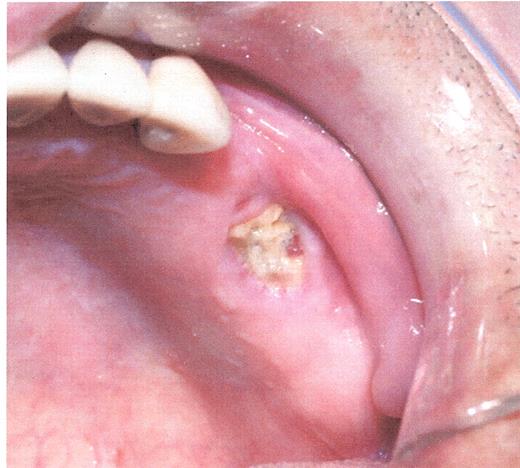

Stage I osteonecrosis of the jaw (ONJ). Patient with myeloma on zoledronic acid for 18 months.